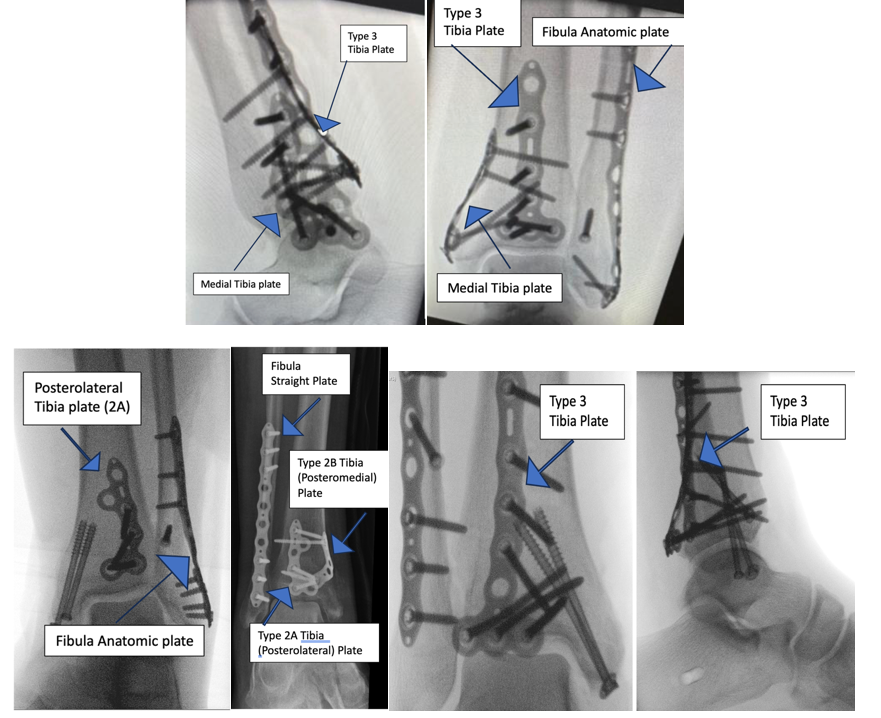

Fragment-specific fixation is usually indicated in cases where stabilization of specific articular segments is required However there is not much published and lack of evidence on fragment specific fixation of trimalleolar fractures.  We reported our experience and early results of fixing these fractures with direct approach using fragment specific implant. (Fig3)

Fig 3 Radiographs showing different type of fixation with fragment   specific plates (Volition TM ).